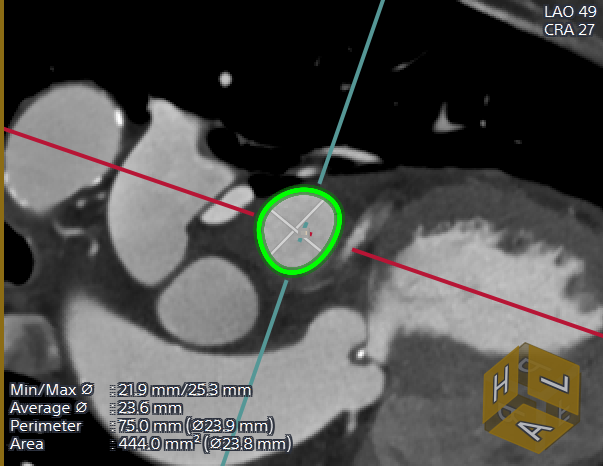

主动脉根部CTA评估

由于患者高龄,术前未行TEE检查,CTA检查后,提示患者左心耳内无血栓。多平面肝位重建分析患者左心耳开口24.6mm,模拟TEE检查左心耳开口21.5mm-24.7mm,左心耳口部封堵面分析平均开口直径24mm,肺静脉脊较长,左心耳深度较浅,拟选用WATCHMAN FLX™ 31mm封堵器封堵。